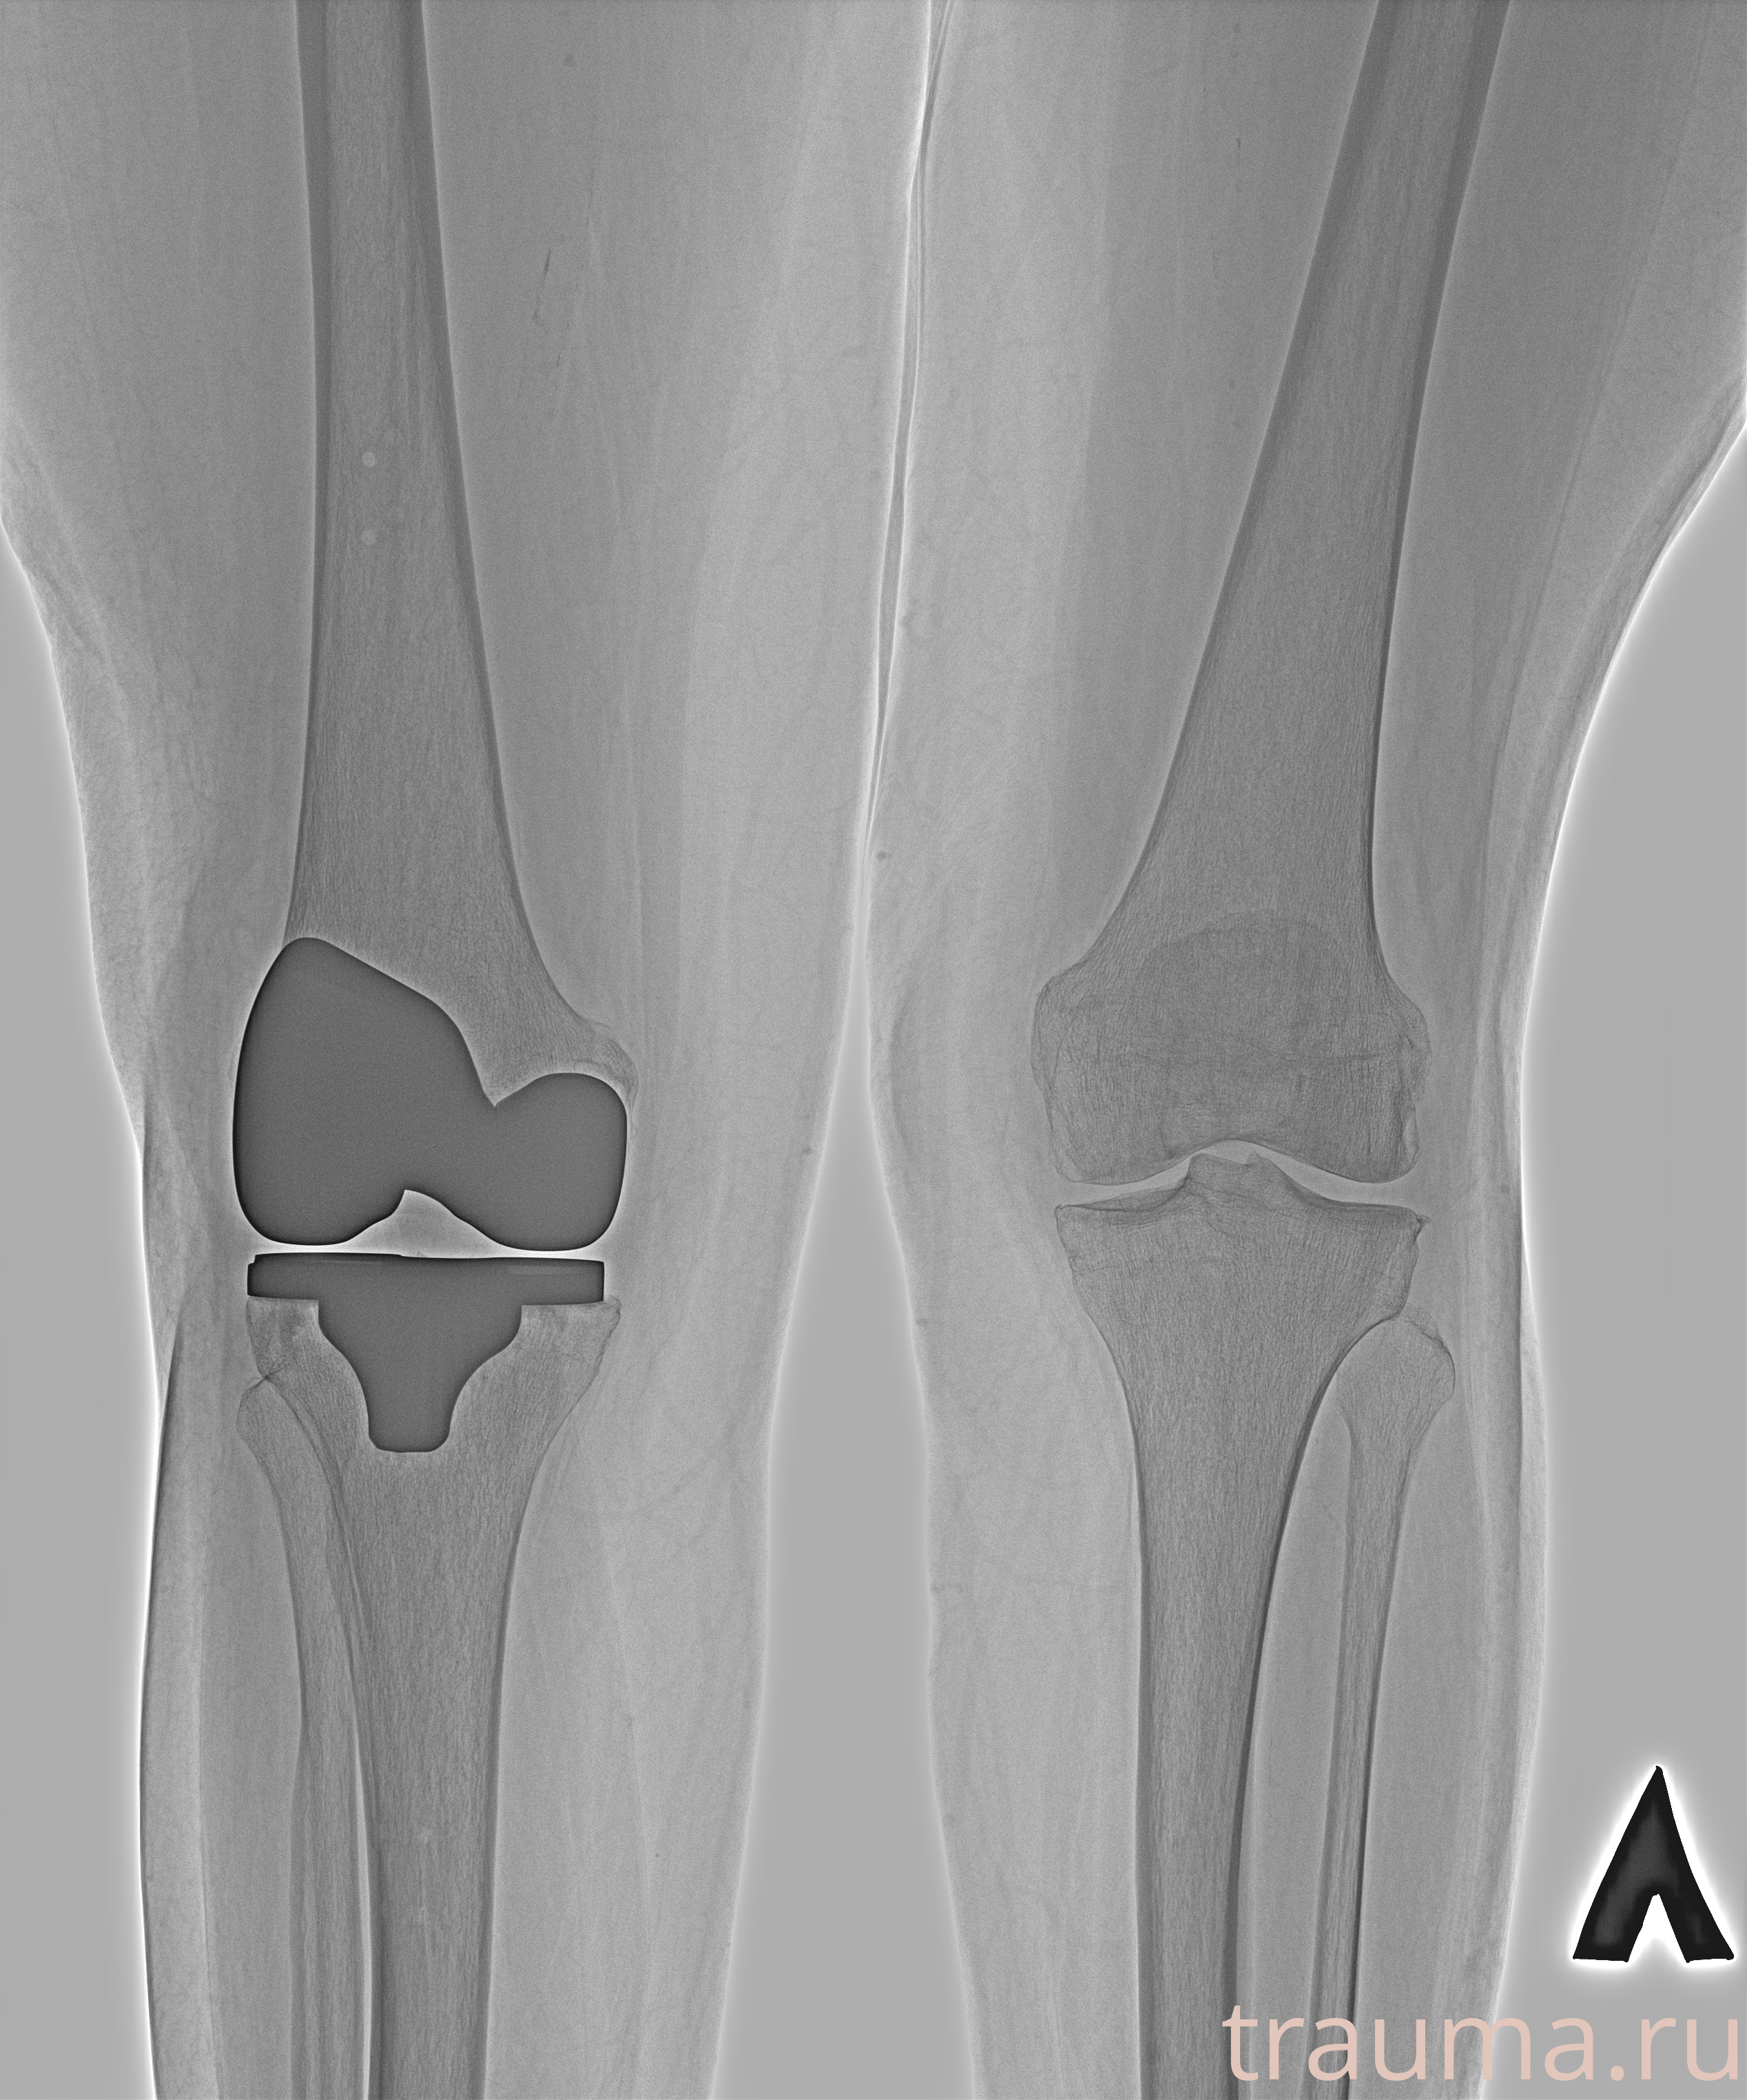

Рентгенограммы

Рентген на дому: по вашему адресу приезжает врач-рентгенолог, травматолог-ортопед с мобильным рентгеновским аппаратом, проводит диагностику травмы или заболевания, делает необходимые рентгенограммы, дает рекомендации по дальнейшему лечению. Получить качественные снимки в домашних условиях возможно благодаря уникальной методике, разработанной МосРентген Центром для института  Склифосовского